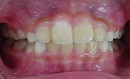

矯正前 矯正後

今回も治療には、独自の方法とビムラー装置等を利用しました。

咬合バランスをよくする為には、

顎を大きくするだけでは不十分と考えています。

その為、かみ合わせの高さなどを立体的に改善していく事を心がけて治療しています。